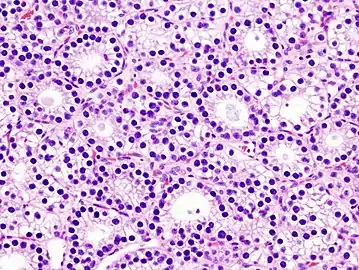

- Histopatholgical image of parathyroid adenoma in a patient with primary hyperparathyroidism. Hematoxylin and eosin stain.